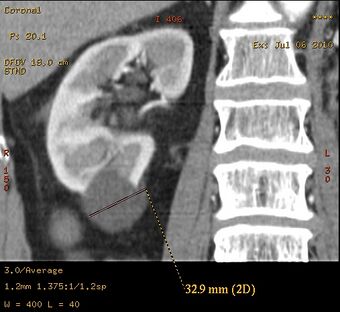

Diagnosis includes imaging with ultrasound, CT and/or MRI. The least expensive, non-invasive, and most reliable method is ultrasonography but smaller cysts may escape detection, while the resolution of CT and MRI will enable smaller cysts to be captured. However, the increased complexity and expense of CT and MRI is usually reserved for higher risk situations. MRI can be used to monitor the development of cysts and growth of kidneys.[citation needed]Genetic test can be applicable to those who have a family history of PKD but is expensive and fails to detect PKD in 15% of cases where it is present. [citation needed]